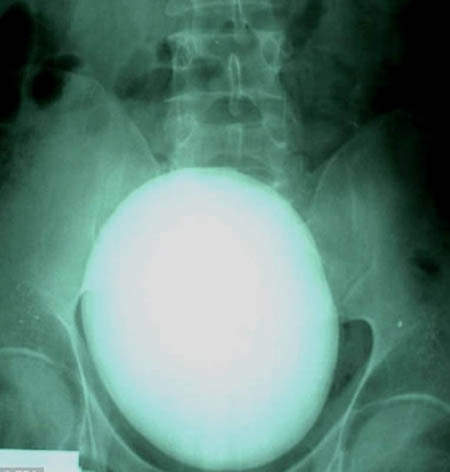

15cm大的腎臓結石

圖片來自:http://www.po-kaki-to.com/